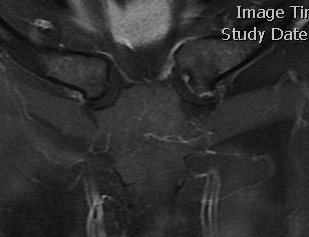

CT

Sternoclavicular Hyperostosis

Bilateral condition

- ossification of sternoclavicular ligaments

- may lead to solid ossification with restriction of shoulder motion